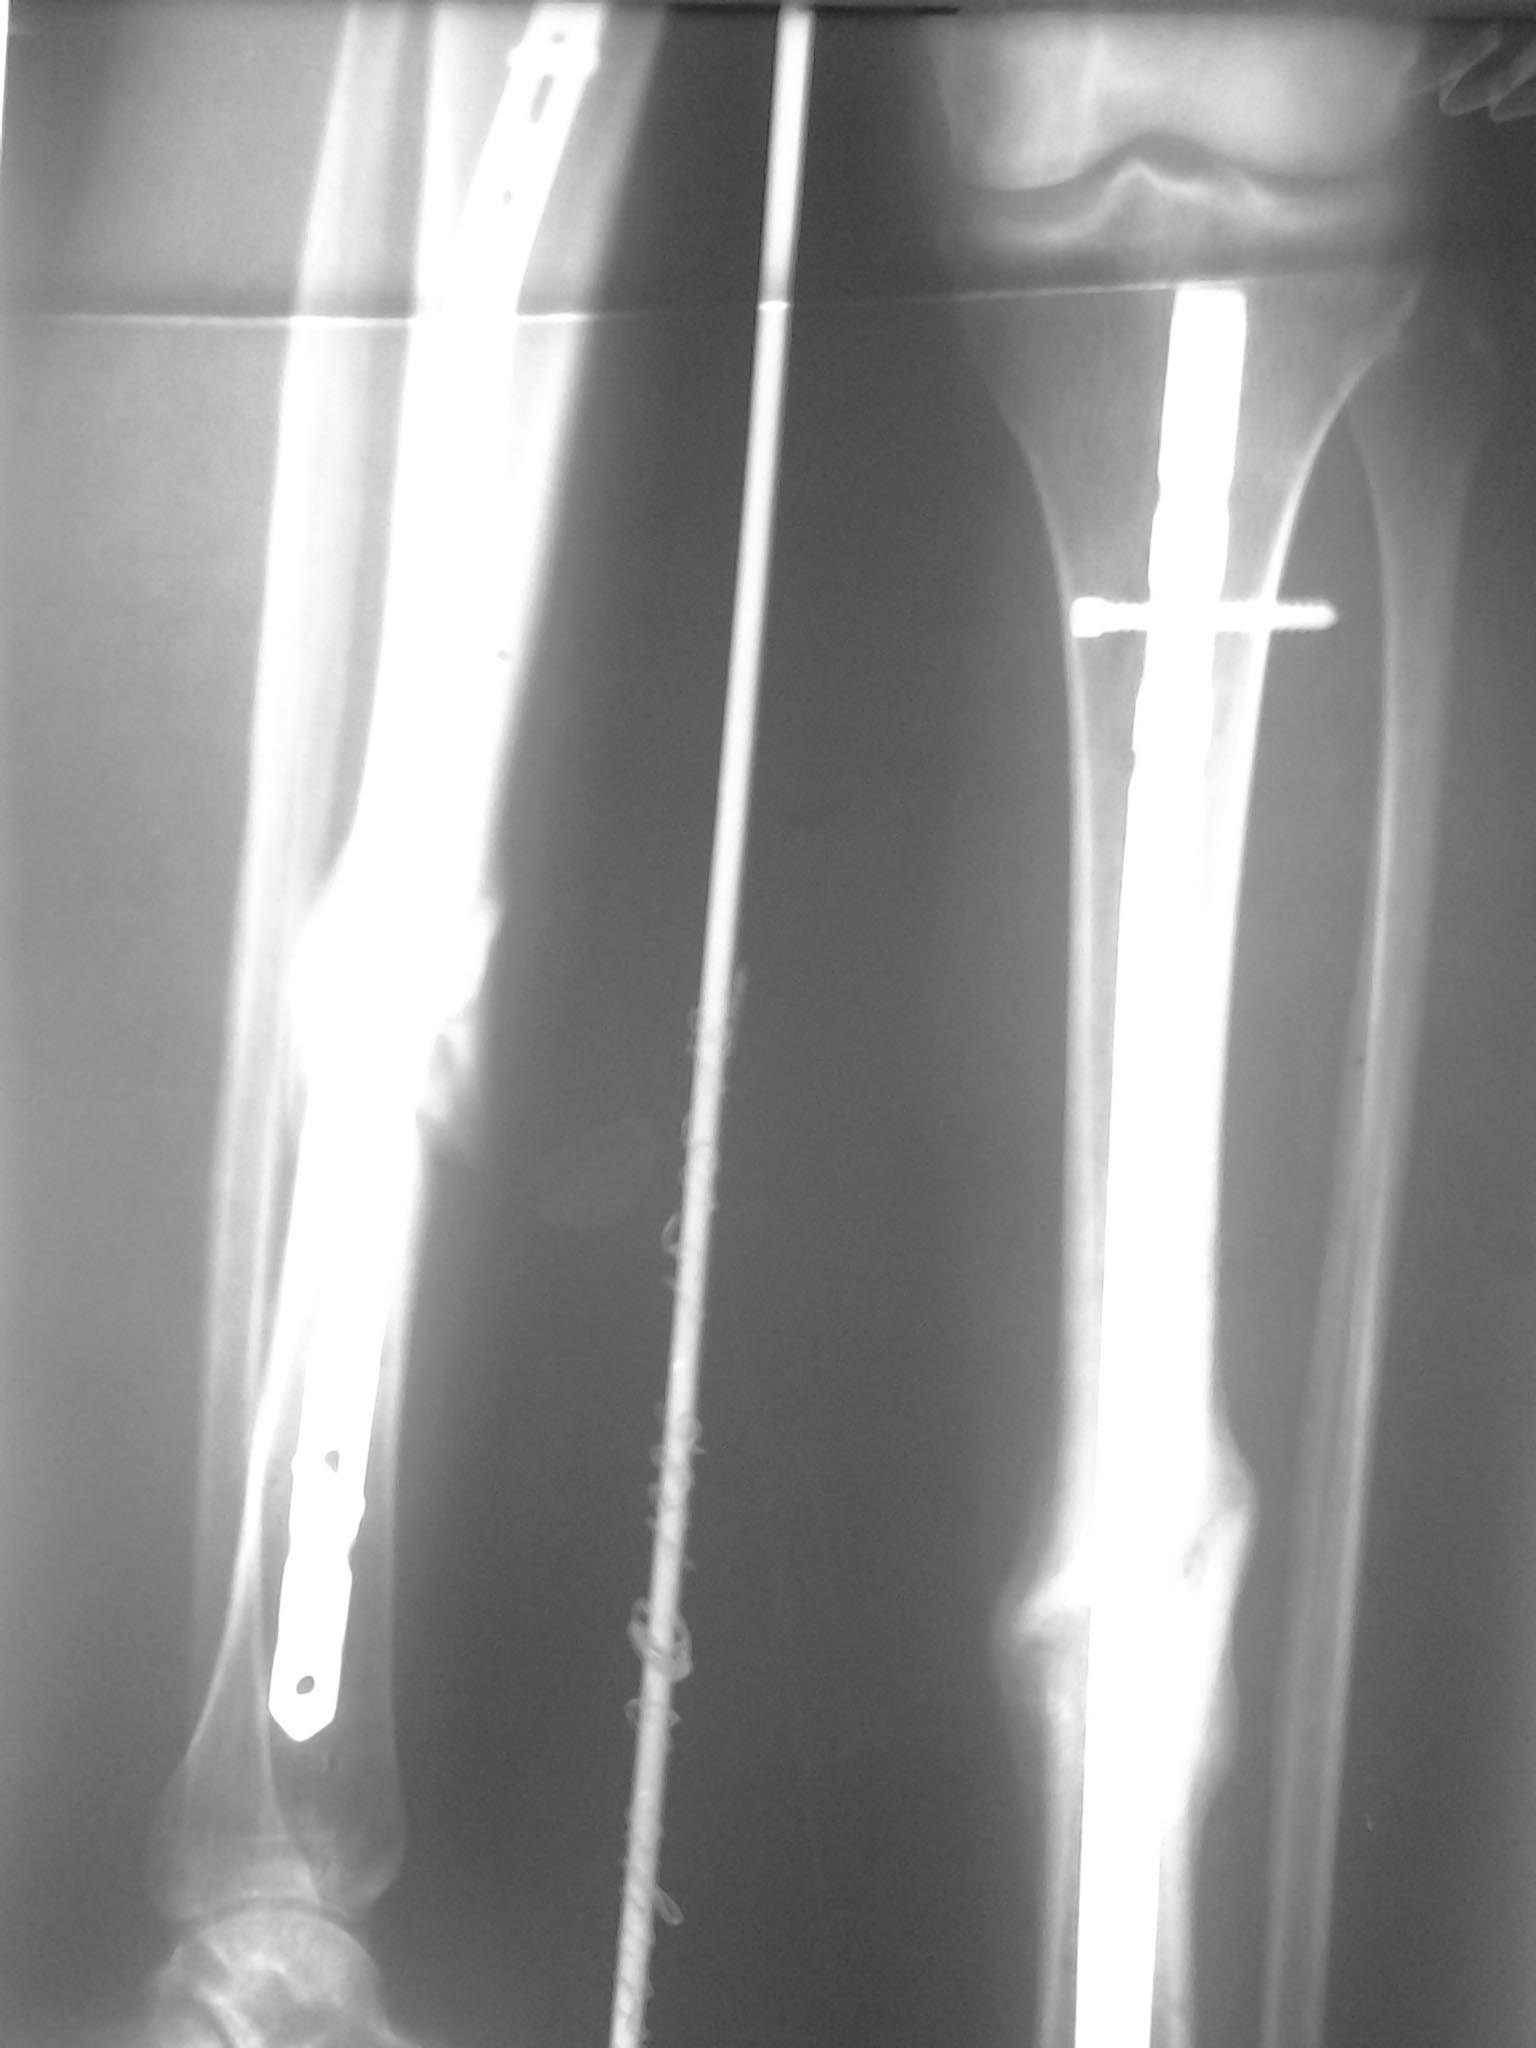

Re: ложный сустав б/берцовой кости на БИОС

общаяя картинка, выложенная щель между отломками прослеживается на протяжении всего периода сращения.